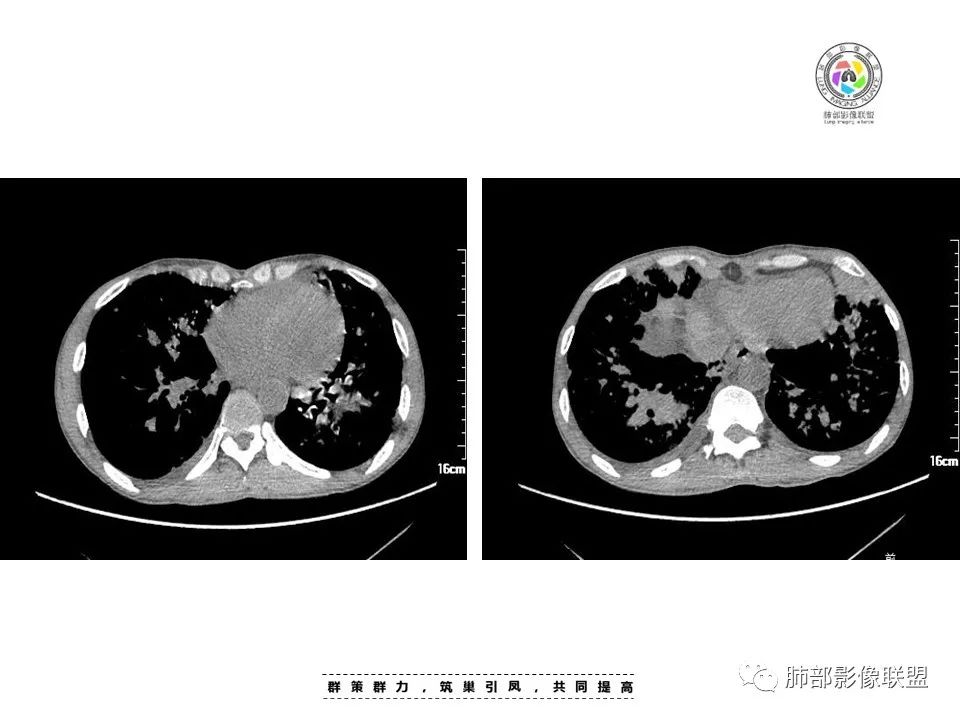

周一晚读病例:男性45岁,发热、纳差,全身散在暗紫色皮疹,结合CD4,符合HIV;肺部影像表现:两肺散在实性结节及磨玻璃密度影,实性结节伴晕征,部分沿支气管血管束分布,支气管血管束增粗,以两肺下叶为著,类似火焰征,双侧胸腔少量积液;首先考虑卡波西肉瘤,鉴别淋巴瘤增值性病变,淋巴瘤样肉芽肿/淋巴瘤,最后挂上马尔尼菲青霉菌病。

中年男性,发热、全身散在暗紫色丘疹,查CD4+T细胞64个/ul,临床信息提示AIDS并发卡波西肉瘤;CT提示双肺多发实性结节影及毛玻璃结节,部分呈点晕征,右上肺大姐姐边缘膨隆、分叶伴晕;双下肺结节沿支气管血管束分布,中轴间质增粗,部分支气管堵塞,叶间裂结节状增厚,部分结节胸膜下分布,可疑局部小叶间隔增厚,肺部病变呈淋巴分布特点,结合临床肺部病变考虑肺卡波西肉瘤,鉴别淋巴瘤。

两肺弥漫性性结节状、小片状及片状带晕的病灶,煎蛋征、点晕征,主要分布两肺中下叶,病灶周围小叶间隔增厚呈网格状影,部分病灶累及胸膜,伴两侧胸膜增厚。

2.本例双肺小叶间隔增厚明显,多发结节影及片状实性密度影,沿血管支气管束分布为主,两侧较为对称,病灶多环以磨玻璃晕,边界不清。

双侧胸腔少量积液。双肺门及纵隔未见明确肿大淋巴结,纵隔结构间隙模糊。